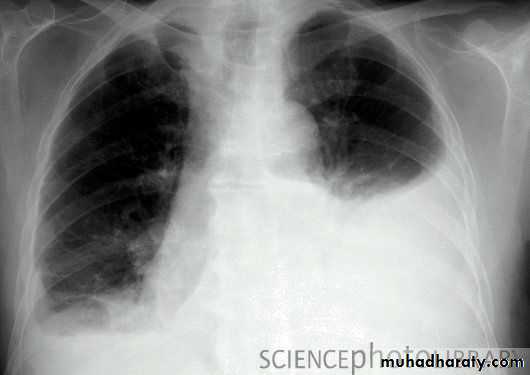

Hemothorax

Patient with fever, rigor and dyspnea